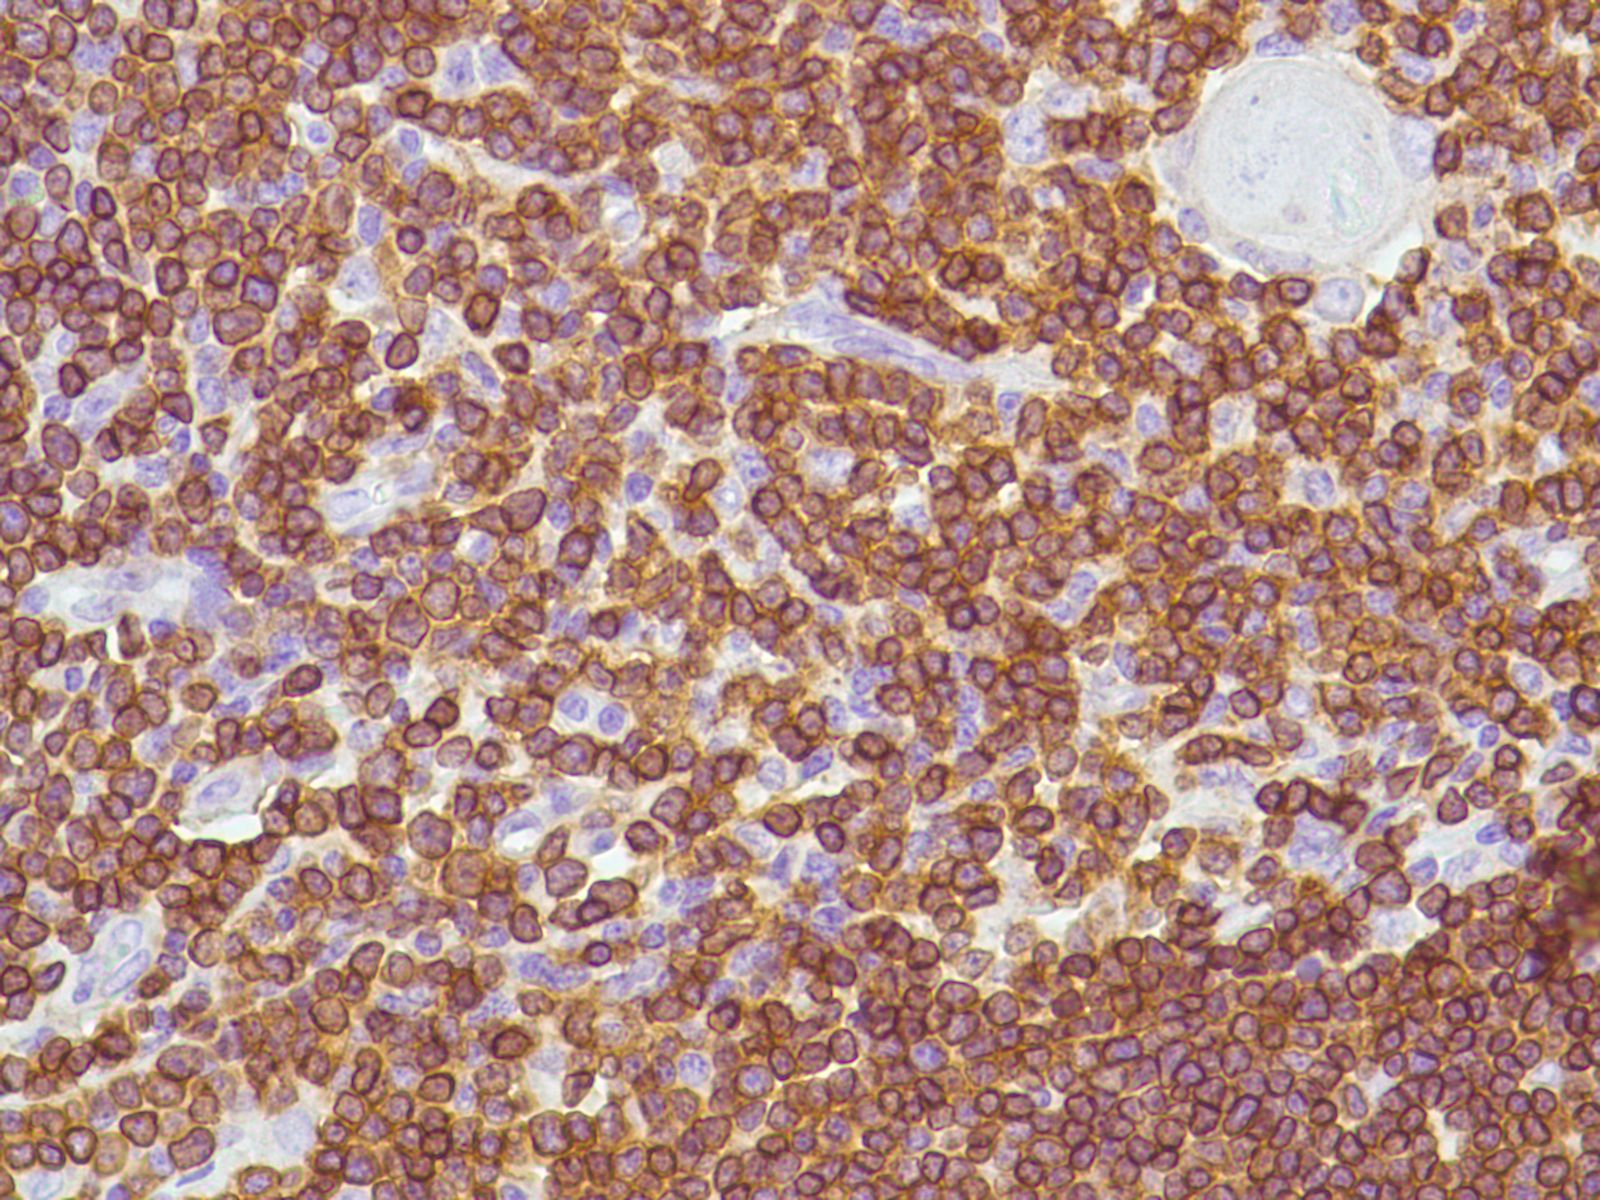

CD3

Species: Dog, Cat.

General information about when this test is indicated:

CD3 is part of the T-cell receptor, the critical part of T-cells responsible for recognising antigens presented by other cells. Therefore, this antibody recognises lymphocytes of T-cell lineage (including CD4+ and CD8+ cells). It may also label Natural Killer cells, and cerebellar Purkinje cells (although the latter can be distinguished by location and morphology). This antibody is used to confirm and characterise diagnoses of T-cell lymphoma, and to help rule out lymphoma in cases of poorly differentiated “round cell” tumours. It is typically used in conjunction with a B-cell antibody (e.g. CD20 or CD79a).

This is helpful because the prognosis and treatment for different forms of lymphoma varies according to their classification. There are low-grade T- and B-cell lymphomas that may have a fair to good prognosis, medium-grade B-cell lymphomas that are often chemoresponsive, and high-grade T-cell lymphomas that may be poorly chemoresponsive and may have a poor prognosis.